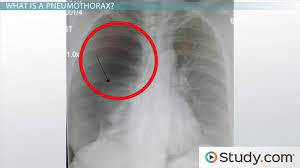

Pneumothorax X Ray / Pt Trick For Pneumothorax Types Symptoms Risk Factors Causes And Treatment Of Collapsed Lung Ezmed : The air then fills the space outside of the lung, between the lung and chest wall.

Pneumothorax X Ray / Pt Trick For Pneumothorax Types Symptoms Risk Factors Causes And Treatment Of Collapsed Lung Ezmed : The air then fills the space outside of the lung, between the lung and chest wall.. Air can enter the pleural space by two mechanisms, either. Jul 02, 2021 · a collapsed lung occurs when air escapes from the lung. Search only for pneumothorax x ray The degree of collapse determines the clinical presentation of pneumothorax. The air accumulation can apply pressure on the lung and make it collapse.

Pneumothorax Undergraduate Diagnostic Imaging Fundamentals from undergradimaging.pressbooks.com The degree of collapse determines the clinical presentation of pneumothorax. The air then fills the space outside of the lung, between the lung and chest wall. The air accumulation can apply pressure on the lung and make it collapse. Search only for pneumothorax x ray It occurs when air accumulates between the parietal and visceral pleurae inside the chest. Air can enter the pleural space by two mechanisms, either. Jul 02, 2021 · a collapsed lung occurs when air escapes from the lung. Nov 16, 2020 · a pneumothorax is defined as a collection of air outside the lung but within the pleural cavity.